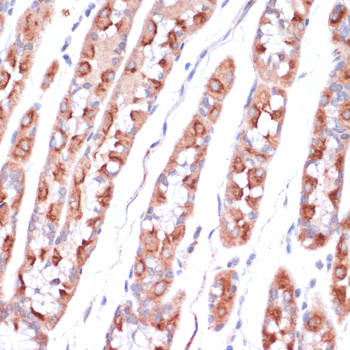

Immunohistochemistry of paraffin-embedded human stomach using UBE2O antibody.

应用详情:IHC 1:50 - 1:200